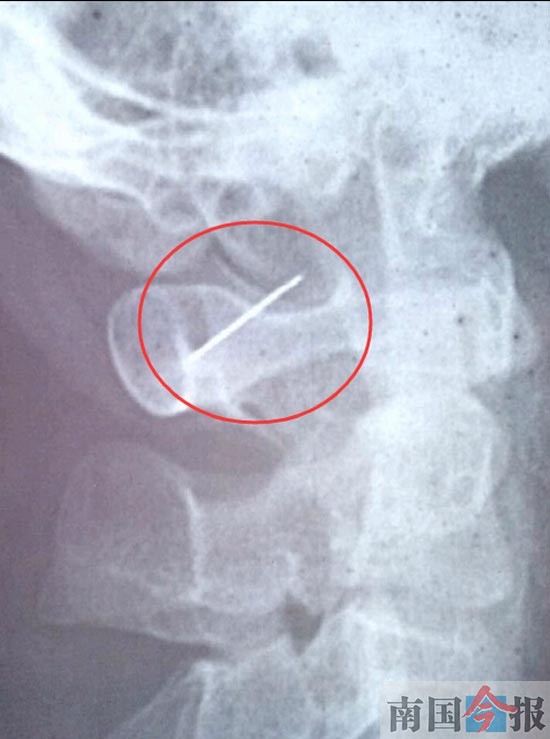

男子靠上枕头准备休息 5厘米缝衣针插进脖子(